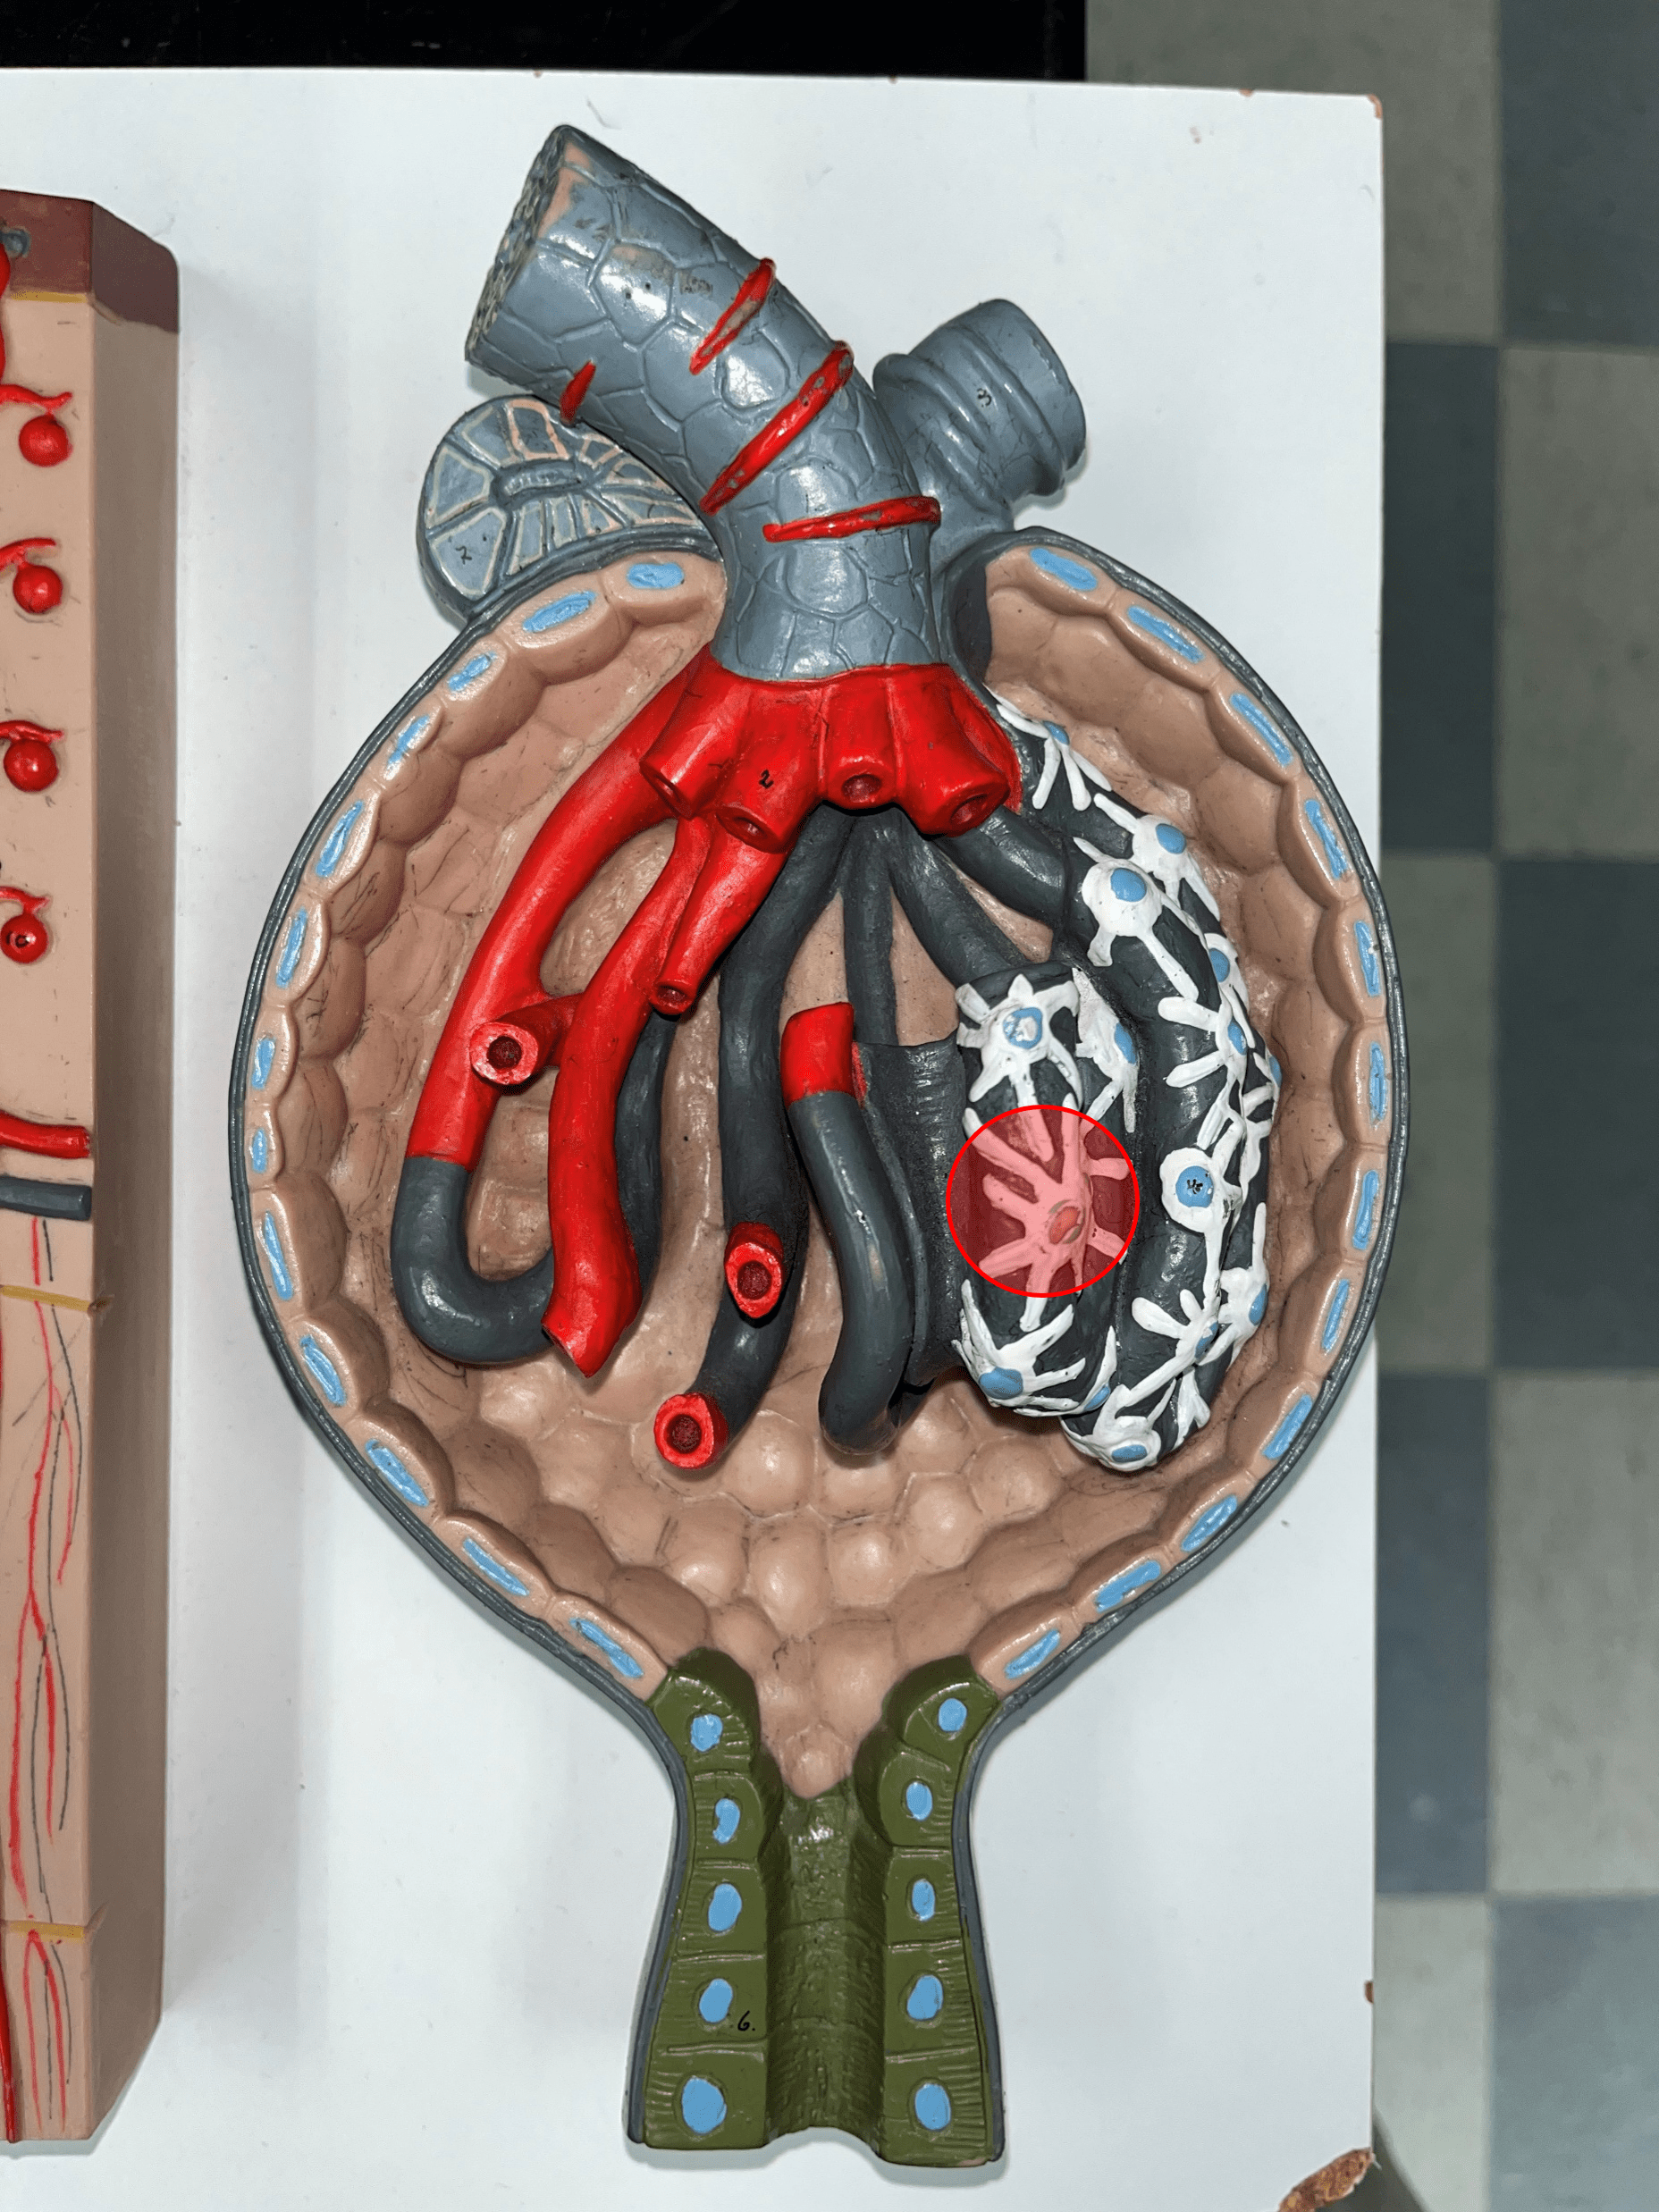

glomerulus

• Slide histology of the nephron.

• Part of a renal corpuscle.

• The capillary network of a renal corpuscle.

• Part of a renal corpuscle.

• The capillary network of a renal corpuscle.

renal corpuscle

• Part of a nephron.

• Filters blood.

• Composed of a glomerulus enclosed within a glomerular capsule.

• Filters blood.

• Composed of a glomerulus enclosed within a glomerular capsule.